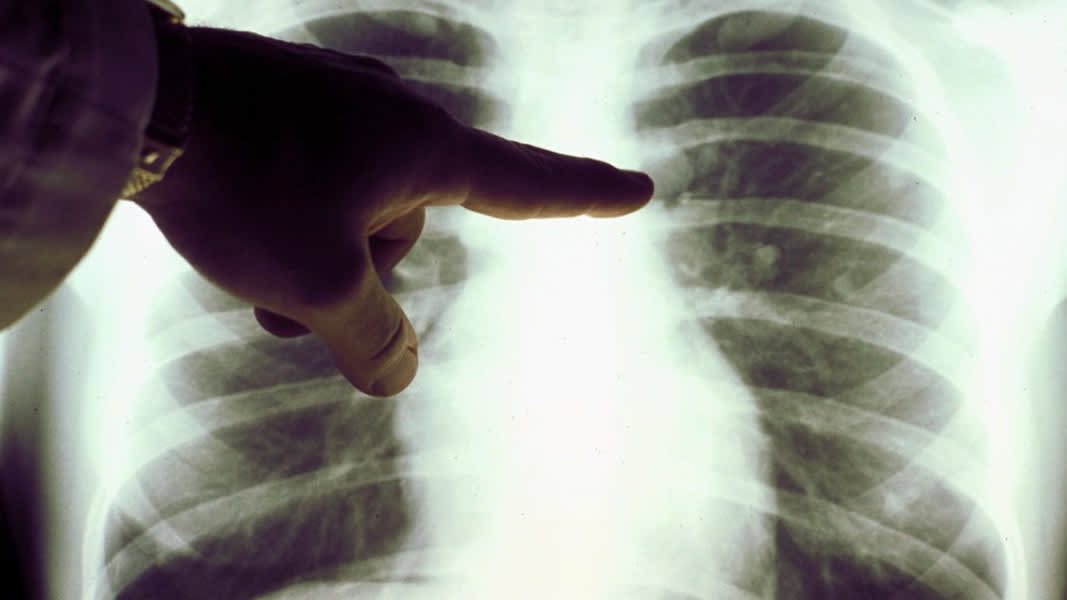

أخطرها التدخين، أسباب الإصابة بسرطان الرئة، ومتى يشعر المريض بالأعراض؟

يحدث سرطان الرئة عندما تنقسم خلايا الرئتين بشكل لا يمكن السيطرة عليه، مما يتسبب في نمو الأورام، ويمكن لأي شخص أن يصاب بسرطان الرئة، ولكن تدخين السجائر والتعرض للدخان أو المواد الكيميائية المستنشقة أو السموم الأخرى يمكن أن يزيد من خطر الإصابة.

لا يعاني الأشخاص المصابون بسرطان الرئة عادةً من الأعراض حتى مرحلة لاحقة، عندما ينتشر السرطان، ومع ذلك تشمل الأعراض المحتملة: